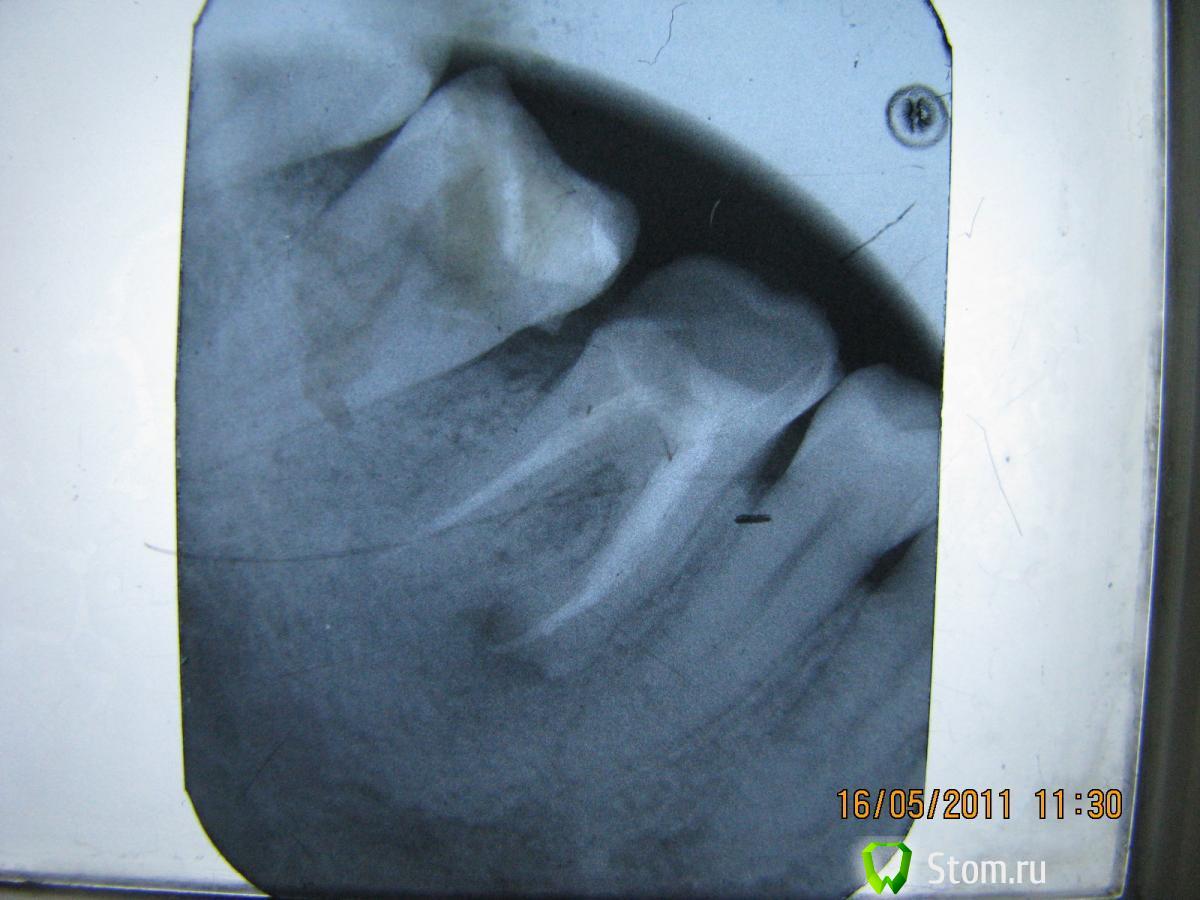

светляк Опубликовано 15 января, 2012 Поделиться Опубликовано 15 января, 2012 Здравствуйте,коллеги.Не знаю,можно ли назвать экспериментом мой случай или все-таки желание сохранить зуб...: Молодая девушка. Зуб 46-резорциненный-не беспокоил,но коронковая часть разрушена почти полностью(если не учитывать старую ,ужасную пломбу без намека на всякую анатомию).На снимке-резорбция медиальных корней.Конечно,с моей стороны последовало предложение удалить зуб и не рисковать,но пациентка пожелала рискнуть("удалить всегда успею"). И с согласия пациентки со всякими расписками о безгарантийном лечении мы начали лечение,которое продолжалось где-то 4 месяца.Была проведена эндодонтия,заложен каласепт и меняла я кала септ на протяжении лечения 3 или 4 раза.Через 4 месяца,увидев,что разрежение уменьшилось,я запломбировала каналы окончательно.Затем-культевая вкладка и коронка. Вложения-приличные.Но иначе восстановить не получилось бы. Ссылка на комментарий

светляк Опубликовано 15 января, 2012 Поделиться Опубликовано 15 января, 2012 Коллеги,извините,за качество.Ну не очень я дружу с отправкой снимков... Смотреть снимки надо в такой последовательности: 1-5-6-2-3-4. Ссылка на комментарий

Scrabble Опубликовано 15 января, 2012 Поделиться Опубликовано 15 января, 2012 Почему эксперимент? У Вас вполне спасабельный зуб был в работе. Только смысл вести на кальции 4 месяца. После снятия острой симптоматики сразу пломбируете постоянно, потом ВКВ, коронка и контроль через 6,12 месяцев Ссылка на комментарий

светляк Опубликовано 15 января, 2012 Поделиться Опубликовано 15 января, 2012 Хотела понаблюдать,будет ли положительная динамика,поскольку культевая+м/к -недешевое удовольствие.Плюс ко всему,после распломбировки он дал обострение,думала удалять придется...Но ,обошлось. Ссылка на комментарий